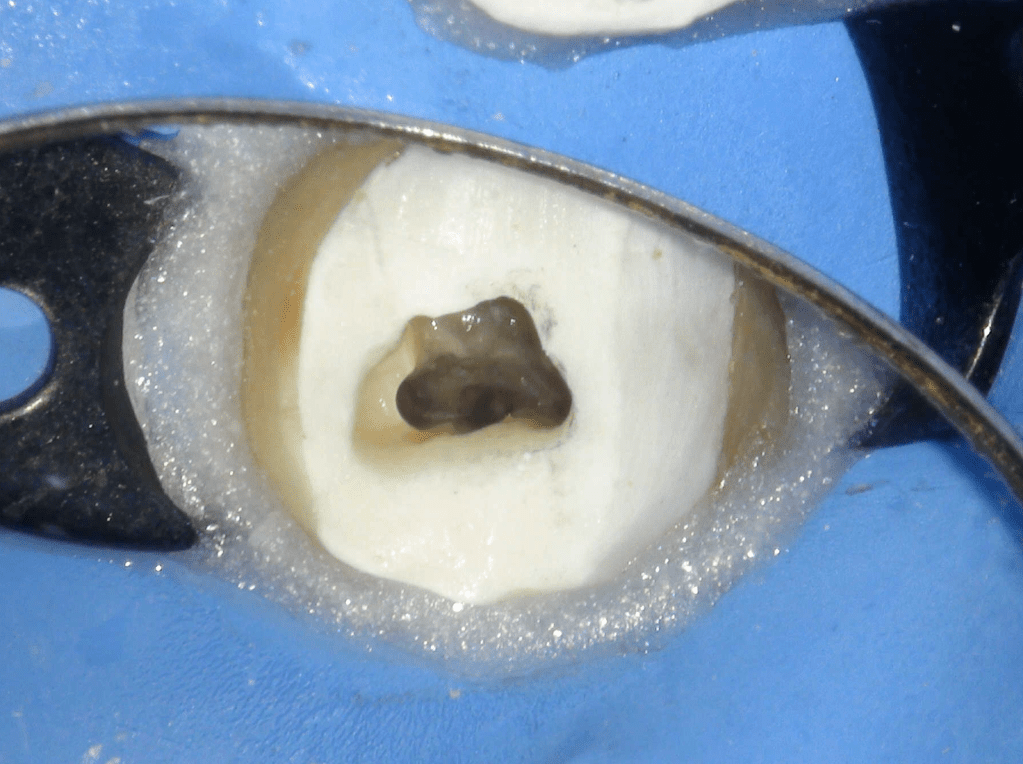

Pulpotomía biodentine + reco preendio